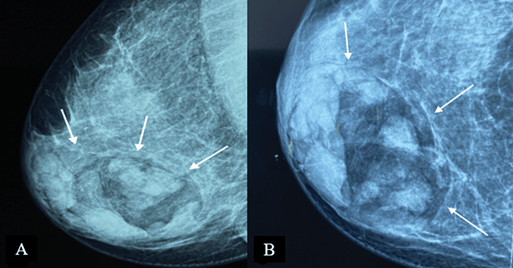

On mammography, MH is typically seen as an inhomogeneous oval or round formation, with radio-opaque and radiotransparent areas that reflect the presence of tissues of different densities (Figure 2). The lesion bears a thin, well-defined radiopaque border (pseudocapsule). The presence of different densities within the pseudocapsule tends to create a pathognomonic impression of a “slice of salami” [2, 25] or a bull’s eye [2] or a “breast within a breast” [26].

Figure 2. Digital mammography: medio-lateral oblique (A) and cranio-caudal (B) projections of the right breast – a large, well-defined mass containing radiolucent (fat) and radiopaque (soft tissue) densities can be seen. It is surrounded by a thin radiopaque capsule, presenting a “breast within a breast” appearance. Image credits: El Yousfi Z, El Mansoury FZ, El Bakkari A, Omor Y, Latib R. Breast hamartoma with synchronous contralateral breast cancer: a case report. Cureus 2024; 16(8): e66534. DOI: 10.7759/cureus.66534. Reused under the terms of the Creative Commons Attribution License CC-BY 4.0. (https://creativecommons.org/licenses/by/4.0/deed.en).